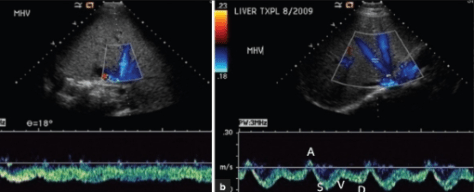

УЗД (доплерографія) судин печінки та судин портальної системи

Ультразвукове дослідження судин печінки досліджує кровоплин в венах та артеріях печінки та оцінює печінкову гемодинаміку при різноманітній патології печінки. Оцінюється наявність і ступень портальної гіпертензії та її форми, тромбозу портальної вени, обхідних судинних шляхів та стан портосистемних шунтів.

Портальна гіпертензія – це стан, для якого характерне стійке підвищення тиску у басейні ворітної вени, зумовлене анатомічною або функціональною обструкцією кровотоку і найчастіше виникає при цирозі печінки. Через цироз кров не може нормально рухатися через печінку і кров починає скидатися по обхідним судинним шляхам. Портальна гіпертензія супроводжується збільшенням селезінки, варикозним розширенням вен стравоходу і шлунка, асцитом, печінкову енцефалопатію.